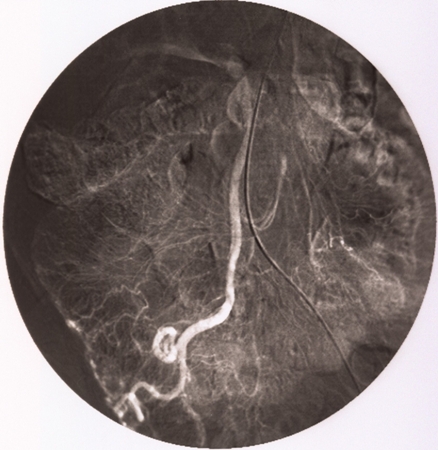

In patients with acutely bleeding lesions (equivalent to 3 units of blood loss per day) and non-diagnostic colonoscopy, CT angiography should be performed to assess the arterial anatomy and localise the bleeding point, followed by mesenteric angiography with a view to embolisation.[39][Figure caption and citation for the preceding image starts]: Ileocolic artery on mesenteric angiogram. Vascular tufts and tangles from local mass of irregular vessels displayedImage donated by Dr DeNunzio, Derby, UK [Citation ends].

[Figure caption and citation for the preceding image starts]: Ileocolic artery on mesenteric angiogramImage donated by Dr DeNunzio, Derby, UK [Citation ends].